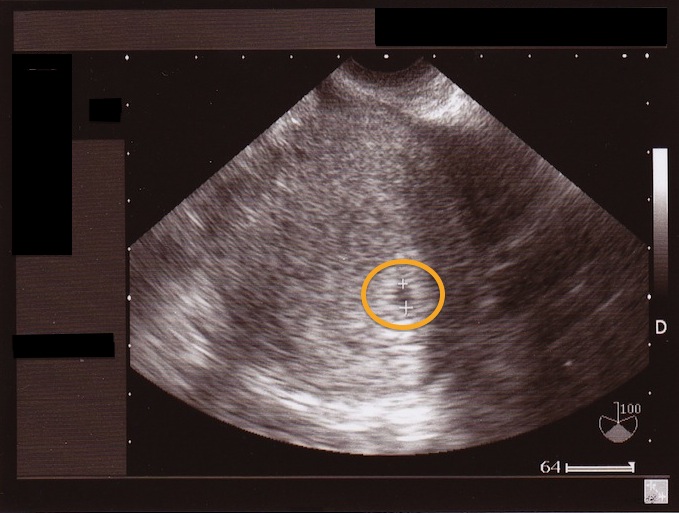

本日婦人科の超音波(エコー)検査にて、

胎芽(妊娠8週未満の赤ちゃんのこと)の着床を確認し

また、M.Aさまより超音波(エコー)写真を見せて頂きました。

御本人にブログ掲載の許可を頂きましたので、ここに御報告させて頂きます。

まだ小さいですが、オレンジ色の丸の中に

胎芽(妊娠8週未満の赤ちゃんのこと)が確認できたとのことです。